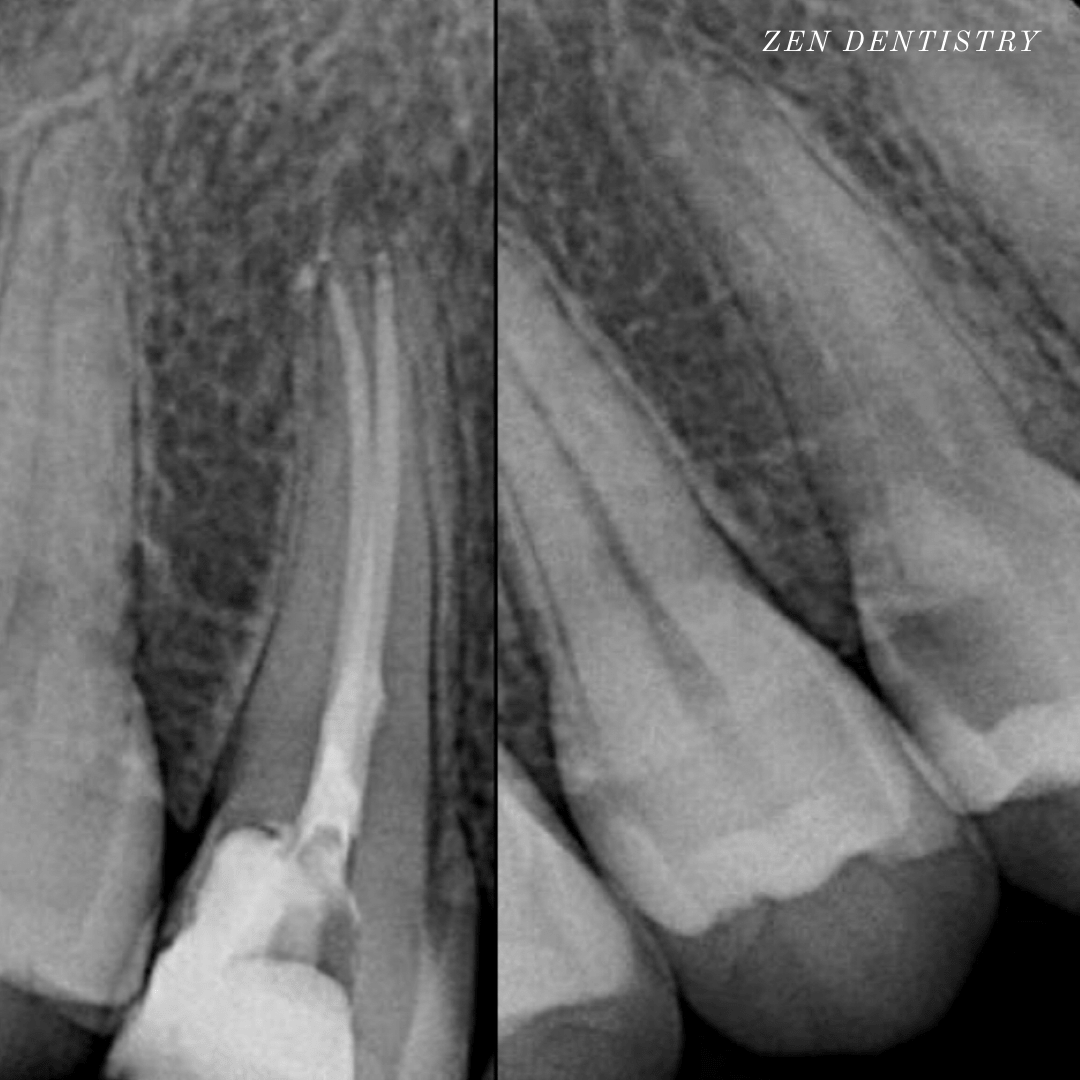

Patient presented to the office with trauma to front two teeth several weeks ago causing her severe pain. After a thorough clinical exam which included endodontic screening and proper x rays led to the diagnosis of necrotic (dead) pulp tissue due to the force of trauma.